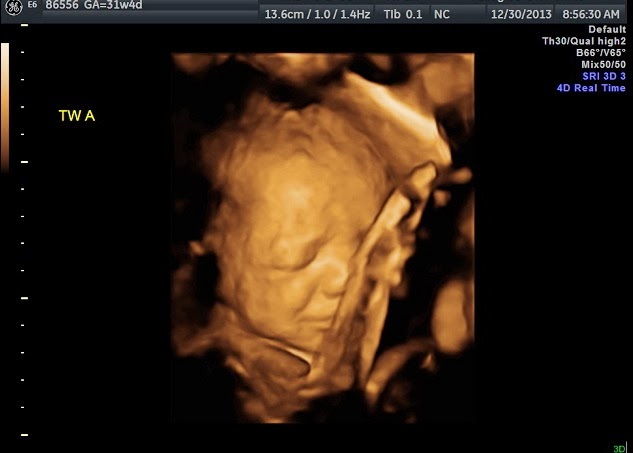

3D Pics (Because they are simultaneously adorable and creepy as hell!)

Baby A

her right hand is up by her forehead and her left arm is bent with her hand behind her neck